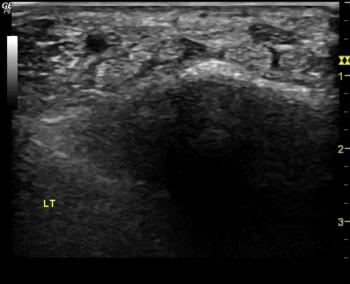

Figure 1. Ultrasound images depicting hydrodissection procedure in a patient with carpal tunnel syndrome. (A) Needle placed below the median nerve with fluid dissecting the nerve from the underlying flexor tendons (green star). (B) Needle placed above the median nerve with fluid dissecting the nerve away from the flexor retinaculum (yellow star). (C) Image at completion of procedure depicting the dissected median nerve with fluid all around. Red Arrow - needle, Blue cross -hydrodissection fluid, white dashed lines - median nerve.

High-res (TIF) version